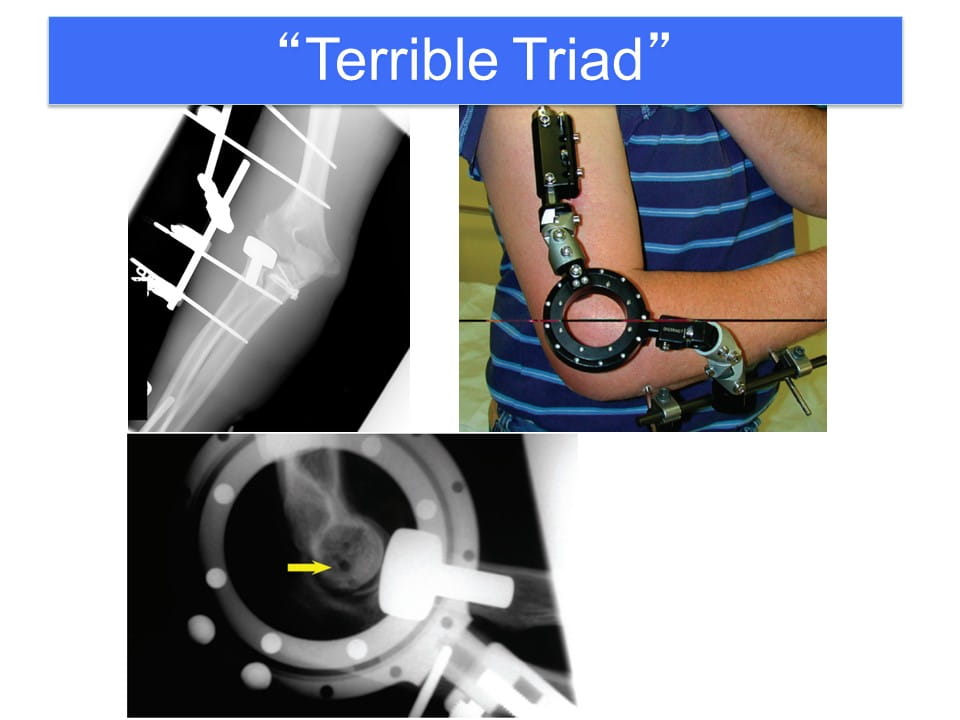

Terrible Triad